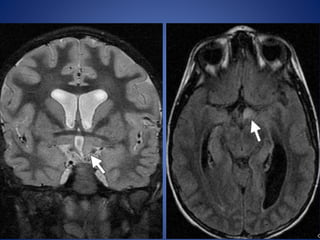

• #12 Pedunculated hypothalamic hamartoma in a 7-year-old girl with thelarche. (a) Sagittal T1WI shows a small, homogeneous, well-delineated round mass (arrowhead) that is isointense relative to gray matter and projects from the hypothalamus.

• #13 the mass (arrowhead) demonstrates no enhancement.

• #14 coronal T2-weighted MR image, the mass (arrowhead) is isointense relative to gray matter

• #18 Hypothalamic glioma in a 6-year-old child with NF-1 and increased linear growth. (a) Coronal short inversion time inversion-recovery and (b) FLAIR images reveal T2 hyperintensity and enlargement of the left aspect of the hypothalamus (arrow).

• #20 Suprasellar germinoma in an 8-year-old girl. (a) Coronal T2WI reveals a heterogeneous mass with hyperintense cystic spaces in the suprasellar region (arrow)

• #21 (b) Axial T1-weighted image reveals an isointense mass with hypointense cystic areas (arrow) splaying the cerebral peduncles

• #22 enhancement of the solid components of the mass (arrow)